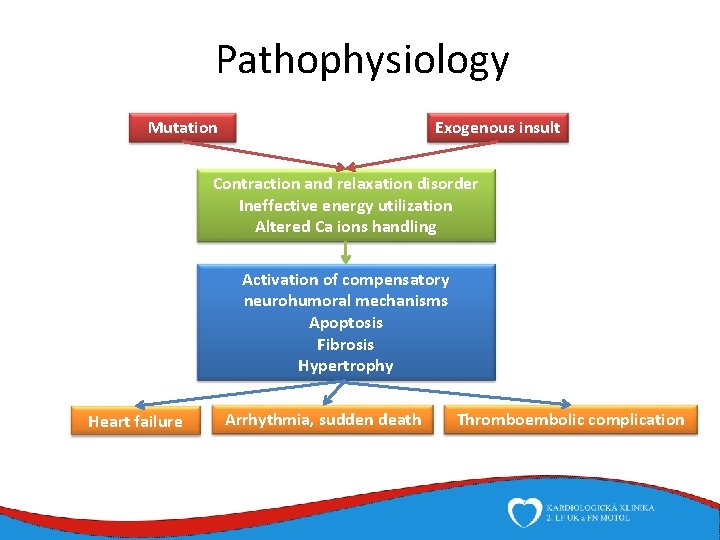

Pathophysiology Mutation Exogenous insult Contraction and relaxation disorder Ineffective energy utilization Altered Ca ions handling Activation of compensatory neurohumoral mechanisms Apoptosis Fibrosis Hypertrophy Heart failure Arrhythmia, sudden death Thromboembolic complication

Etiology Primary dysfunction of cardiomyocytes (by genetic or exogenous insult) Insult leads to disorder of contraction or relaxation Long-standing activation of compensatory neurohumoral mechanisms (eventually accentuates heart failure) Oxidative stress, hypertrophy, fibrosis, apoptosis